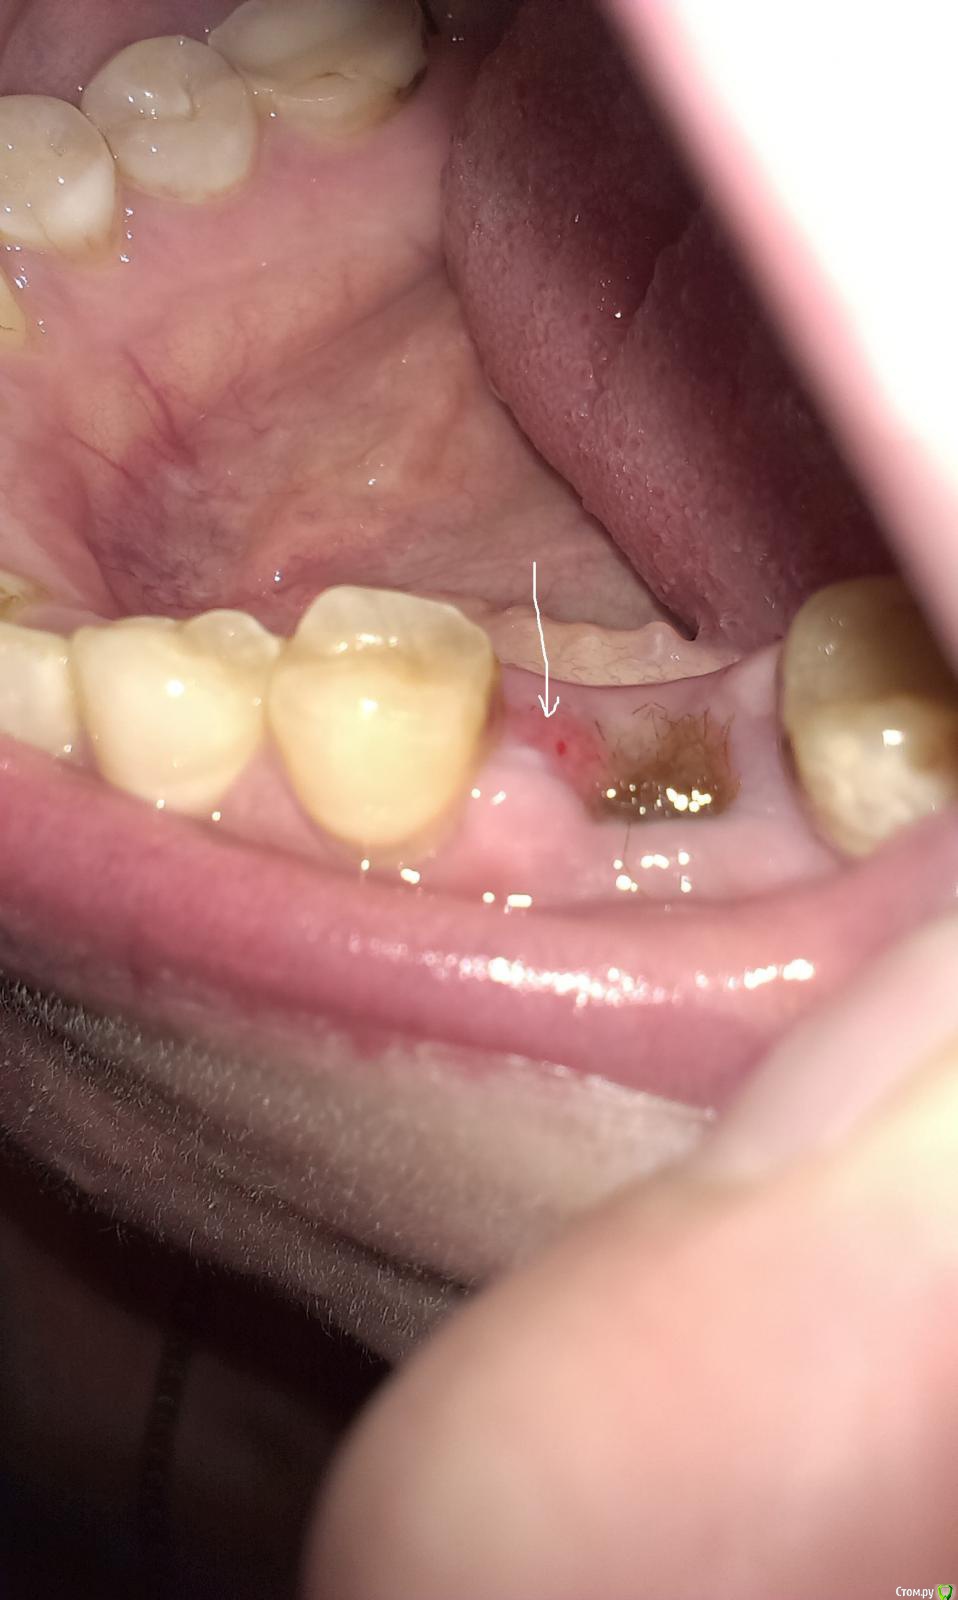

Scream Опубликовано 4 мая, 2015 Автор Поделиться Опубликовано 4 мая, 2015 (изменено) Уважаемые доктора, это снова я.Две недели после удаления. Стало лучше, НО в лунке до сих пор альвожель, чувствую, что мешает. Сегодня пыталась убрать аккуратно ватной палочкой, он глубоко, и сразу лунка стала кровить и болеть. Это вообще нормально, что через 2 недели кровит при дотрагивании? Рентген больше не повторяла, вроде как были улучшения в самочувствии, а сегодня вот такая котовасия. Что делать в этими волокнами и почему они так долго там торчат, я так понимаю,они должны рассасываться? У меня ощущение, что от них только хуже(((ps прошу взглянуть на фото: еще пугает локальная краснота сбоку лунки (это нормальный процесс заживления ткани или что-то не так?). Будьте добры, посмотрите и ответьте, нужно ли снова к доктору. Я так измучилась уже с этим зубом - его уже нет, а он все равно не дает мне покоя и снова начал ныть, потревожила?(( Изменено 4 мая, 2015 пользователем Scream Ссылка на комментарий

kladoffka Опубликовано 5 мая, 2015 Поделиться Опубликовано 5 мая, 2015 Кмк надо сходить к доктору, что бы он убрал альвожил. Им не нужно тампонировать лунку. Ссылка на комментарий

Чертков Александр Опубликовано 5 мая, 2015 Поделиться Опубликовано 5 мая, 2015 Здравствуйте. Все хорошо. Только вот "волосы" надо убрать....уже мешают заживлению. Ссылка на комментарий